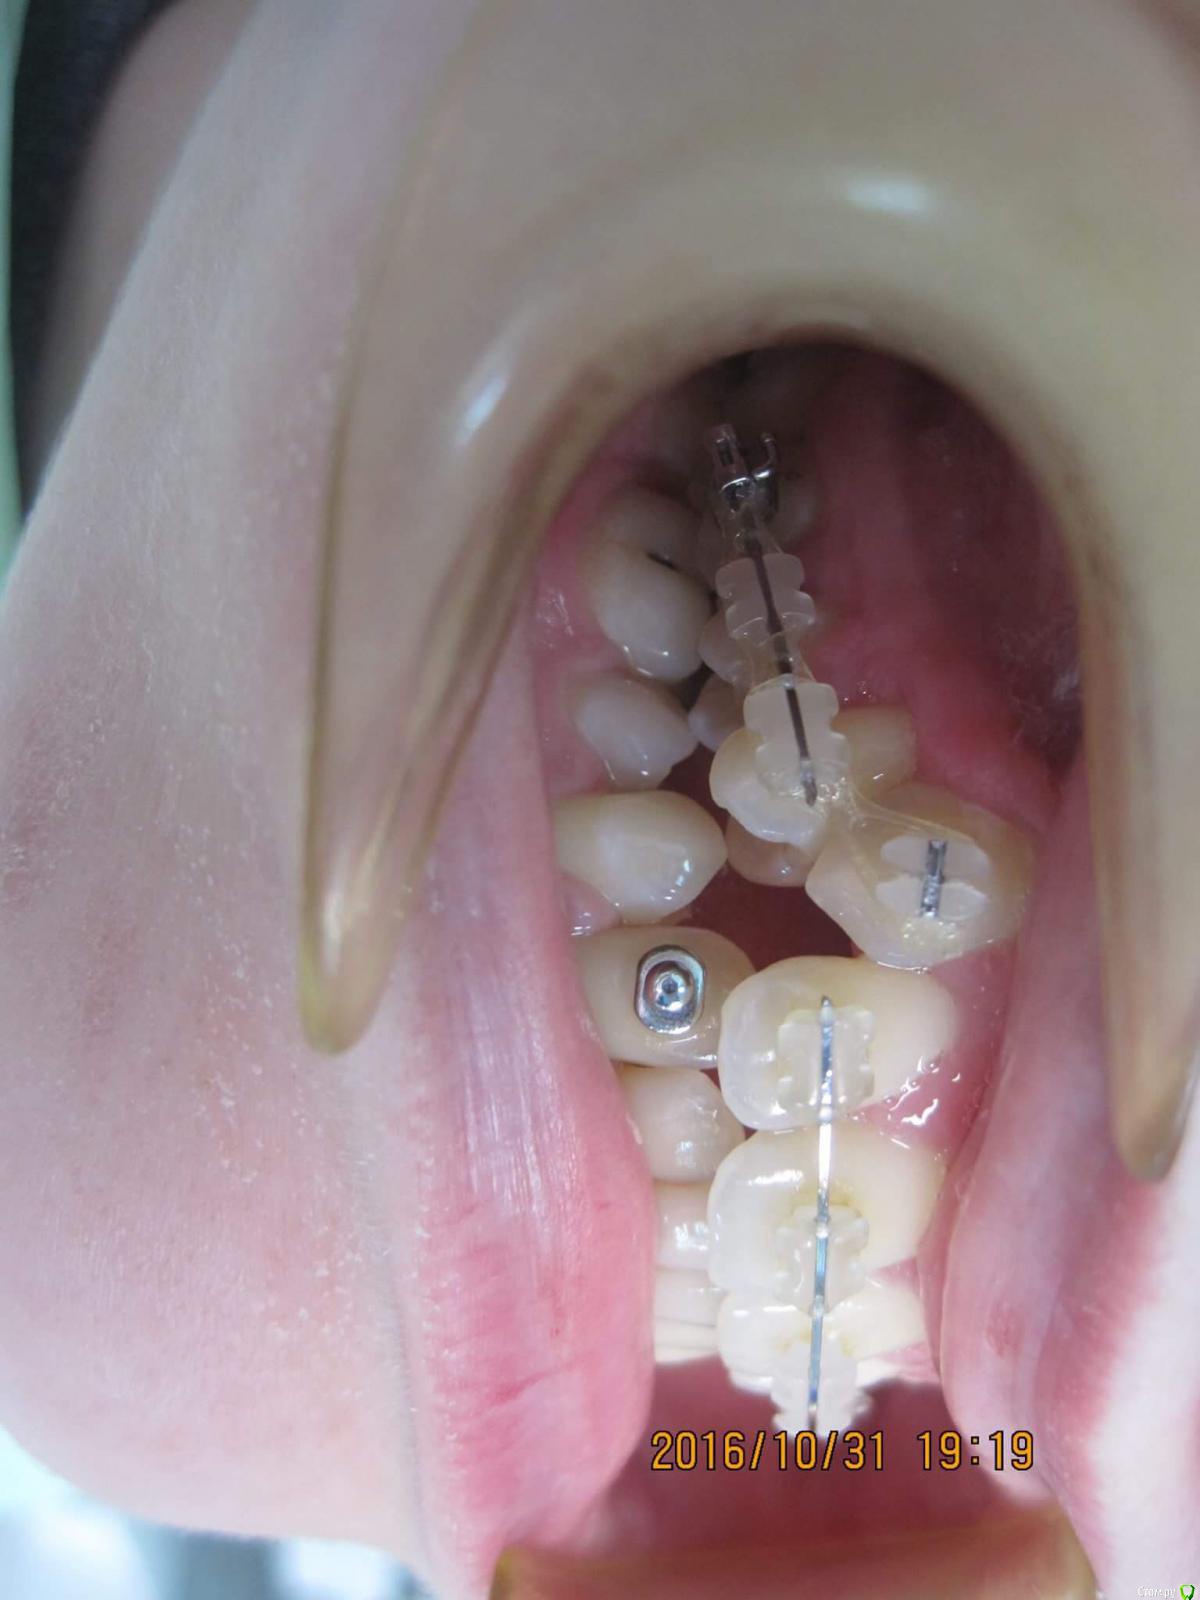

Opdihatop Опубликовано 9 декабря, 2016 Поделиться Опубликовано 9 декабря, 2016 Яна, а на Ваших фото это и есть та самая ballista? Просто никогда еще такой формулировки названия не встречал. Ссылка на комментарий

Yana guapa Опубликовано 10 декабря, 2016 Поделиться Опубликовано 10 декабря, 2016 Яна, а на Ваших фото это и есть та самая ballista? Просто никогда еще такой формулировки названия не встречал. да, она именно так и называется. здесь я 5 ку доставала. после создания место благодаря активному рычагузуб вышел за месяц Ссылка на комментарий

Yana guapa Опубликовано 10 декабря, 2016 Поделиться Опубликовано 10 декабря, 2016 Яна, ballista - круглая сталь, по типу пружины kelroy? Я согнула из тма куском и активировалаиз тма - дорогое удовольствие!)) почти 500рэ! я из 014 SS делаю, 50р)) на зубах - основная дуга (в принципе любая, какая на этапе уже стоит), и плюс сверху подвязать баллисту (так, чтобы завиток был перпендикулярно от вытаскиваемого зуба; и в конце с усилием натянуть петельку к зубу и подвязать лигатурой. )п.с. инфы много по баллисте , пропиши wire ballista Ссылка на комментарий